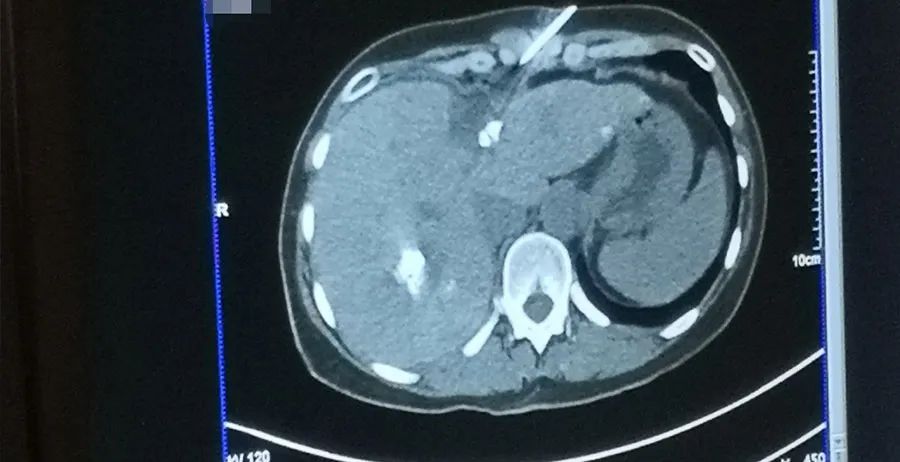

两例肝脏微波消融手术中,第一例为一个3.0cm的病灶,单针消融两次后顺利完成手术。第二例为肝部5个转移肿瘤,使用单针消融五次。“Super good!”,当Lucas教授在术后消融影像中看到5个大小几乎一模一样的圆形消融区时惊叹道!之后,他也不禁多次赞叹Dophi™ M150E微波消融系统带来的精准、一致、可控的消融效果。

术中影像资料